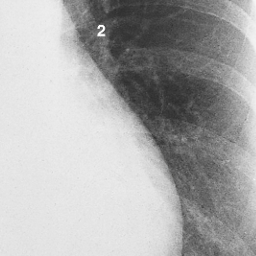

Right and Left diaphragms: difference

The right hemidiaphragm: stretches across the whole thorax and can be clearly seen passing through the heart border.

The left hemidiaphram (2) seems to disappear when it reaches the posterior border of the heart.